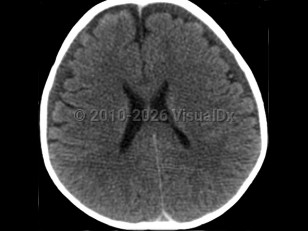

It is thought that the primary injury arises as a result of the multidirectional forces from shaking, leading to a form of whiplash injury associated with diffuse axonal injury, tearing of bridging veins, and subsequent intracranial bleeding. The secondary brain injury is due to a combination of hypoxia, ischemia, and brain edema. The end result is destruction of brain cells, a reduced supply of oxygen to brain cells, and brain swelling leading to varying degrees of neurological deterioration and occasionally death. Anatomically, the combination of a not-yet myelinated brain, a relatively heavy head upon weak neck muscles, and lack of control of the head and neck are factors that predispose babies to this form of injury.

Abusive head trauma may present with one or more of the following clinical features: subdural hemorrhage, retinal hemorrhage, and encephalopathy. Retinal hemorrhages are present in approximately 85% of cases and may be unilateral, but the diagnosis of abusive head trauma should not be excluded if they are absent.

Injuries that raise concern for abusive head trauma – such as severe intracranial injury, with or without retinal hemorrhages, with or without additional injuries, and having an inadequate trauma history to explain the findings – have not been documented in falls from short heights or from routine handling or play with infants such as throwing a baby into the air and catching them.